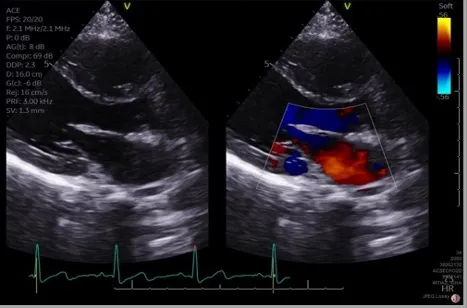

- Echocardiography: Primary diagnostic tool; anatomy & function.

- Echo: Defect. Ausc: Wide, fixed S2.

- Echo: Defect. Ausc: Holosystolic murmur.

- Echo: Ductus. Ausc: Continuous machinery murmur.

- Echocardiography is gold standard for CHD diagnosis and anatomy.